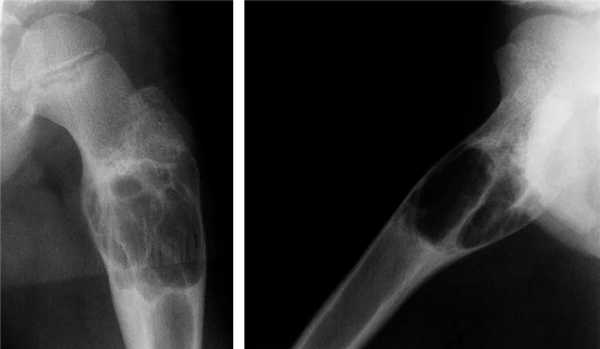

Хондрома. Хондромы, как указывает С. А. Рейнберг, наблюдаются преимущественно в детском и юношеском возрасте По данным Т. П. Виноградовой, возраст больных различен с преобладанием со второго по четвертое десятилетие жизни. Из 52 наблюдаемых нами больных хондромой большая часть пациентов, была в возрасте 30—40 лет. Преобладание какого-либо пола среди больных не отмечается. В большинстве случаев поражаются короткие трубчатые кости кисти (примерно в 70% случаев), реже — стоп, затем кости таза, отростки позвонков, грудина. Длинные трубчатые кости поражаются весьма редко. В длинных трубчатых костях хондрома локализуется в метаэпифизарных концах. По данным И. Г. Лагуновой (1962), в среднем и пожилом возрасте хондрома в длинных трубчатых костях располагается в метафизе, распространяясь в эпифиз или диафиз. В наших наблюдениях превалировала метаэпифизарная локализация хондром. В детском возрасте хондромы в длинных трубчатых костях, как правило, поражают метафиз. В коротких трубчатых костях кисти и стопы хондромы чаще бывают множественными, причем отмечается двустороннее поражение. В плоских костях, и особенно в длинных трубчатых костях, наблюдаются солитарные хондромы. Суставы, как правило, не изменены. Но при больших размерах опухоли наступает выраженная деформация костей, механически препятствующих движениям в суставах.

Рентгенологическая картина энхондром довольно характерна. Определяются округлой и овальной формы очаги деструкции костной ткани. Эти очаги деструкции располагаются или центрально, вызывая вздутие кости, или эксцентрично. На хрящевом фоне могут выделяться одиночные костные перемычки и вкрапления извести. В ряде случаев эти известковые вкрапления бывают множественными, сливаются между собою, и как бы заполняют весь хрящевой фон (очаг деструкции). Кортикальный слой неравномерно истончен, местами утолщен, не прерывается. В длинных трубчатых костях очаг деструкции, располагаясь в метаэпифизарном отделе, вызывает умеренное вздутие кости. Истонченный кортикальный слой, как правило, имеет ровные контуры. Возможна булавовидная деформация пораженного отдела кости. Вследствие поражения эпифизарных хрящей у детей может наблюдаться торможение роста кости в длину. Наблюдаются патологические переломы пораженной кости.

Первичные хондромы костей могут озлокачествляться, чаще озлокачествляются хондромы таза и длинных трубчатых костей. Наиболее опасными в смысле озлокачествления являются энхондромы с преобладанием обызвествлений (3 тип хондром по И. Г. Лагуновой). Наблюдаются также озлокачествления хондром ребер. Существует мнение, что хондромы коротких трубчатых костей кисти не озлокачествляются, хотя они имеют менее зрелое строение, чем хондромы таза. Однако мы наблюдали в двух случаях озлокачествление хондром костей кисти.

Признаки озлокачествления хондром те же, что и других доброкачественных опухолей: нарастание боли, быстрый рост, разрушение кортикального слоя, выход мягкотканной тени за пределы кости, незначительно выраженная периостальная реакция.

Диагностика хондром не представляет больших трудностей, особенно при их локализации в коротких трубчатых костях. При локализации энхондром в длинных трубчатых костях может возникнуть необходимость в проведении дифференциальной диагностики между хондромой и костной кистой. Хондрома преимущественно располагается в метаэпифизарном отделе, в то время как костная киста локализуется в метадиафизарном отделе. Деформация кости при костной кисте приближается к веретенообразной, нет вкраплений извести. Часто первым симптомом костной кисты является патологический перелом, в то время как энхондрома из-за болей обычно определяется до возможного перелома. Сложной бывает дифференциальная диагностика центрально расположенной энхондромы длинных трубчатых костей с хондробластомой, которая обычно располагается в концевых отделах костей. На фоне очага деструкции также прослеживаются участки обызвествления. В отличие от хондромы, вокруг очага деструкции при хондробластоме может иметь место узкая зона склероза и в случаях, если очаг деструкции располагается субкортикально, появляются периостальные наслоения.

Самая трудная дифференциальная диагностика сводится при хондромах к разграничению доброкачественных и злокачественных форм опухолей. Это осложняется тем, что хондросаркомы в ряде случаев характеризуются длительным течением (в нелеченных случаях опухоль может существовать 4—5 лет). В отличие от хондромы, очаг деструкции при хондросаркоме имеет нечеткие, неровные очертания. Хондросаркома прорастает за пределы кости и на фоне мягкотканной тени, вышедшей за пределы кости, определяется крапчатость за счет обызвествлений. В пользу хондросаркомы свидетельствует также характерный периостоз в виде «периостального козырька».